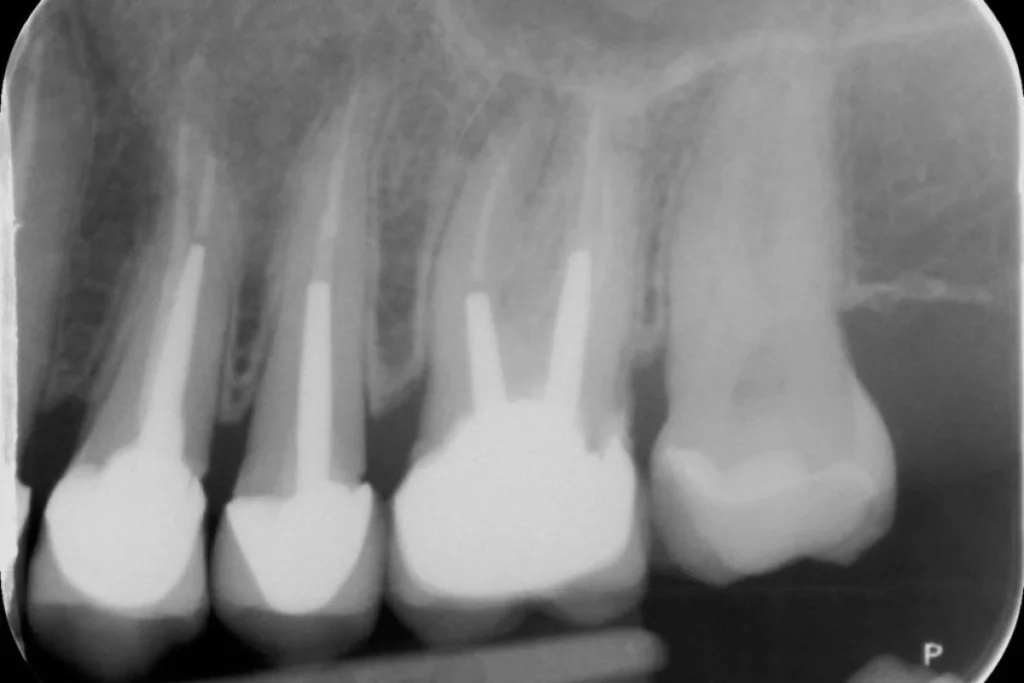

Nous vous présentons le cas de Mme B. 53 ans, qui consulte suite à des douleurs sur sa molaire supérieure gauche.

Après un examen clinique et radiographique, le verdict tombe… la dent n’est malheureusement plus conservable.

Après lui avoir exposé les différentes solutions, Madame B. souhaite remplacer sa dent par un implant. C’est la solution de choix pour retrouver une dent fixe sans avoir à abimer les dents de part et d’autre. L’analyse du scanner nous permet de proposer à Madame B. une extraction implantation immédiate. Il s’agit de réaliser en une seule et même séance l’extraction de la dent condamnée et la mise en place de l’implant dentaire.

Cela permet d’éviter une 2ème chirurgie à notre patiente et de raccourcir la durée du traitement de plusieurs mois. Un comblement osseux est réalisé le jour de l’intervention.

3 mois après la pose de l’implant, la patiente peut retrouver une dent fonctionnelle et esthétique.